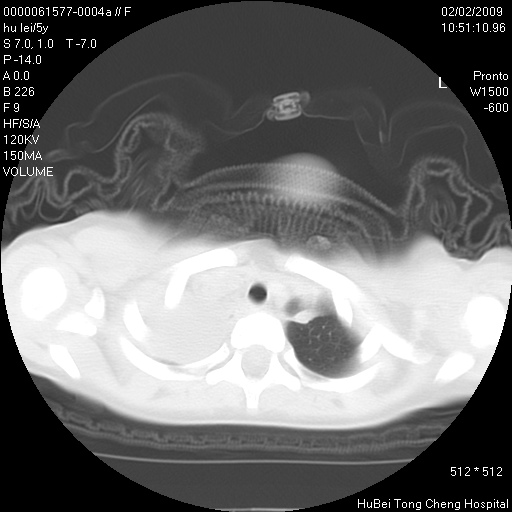

标题: PED1732:M5Y,右肺囊性占位!

患者:男,5。无明显不适,拍胸片考虑右肺囊肿。

行ct扫描,图象如下: